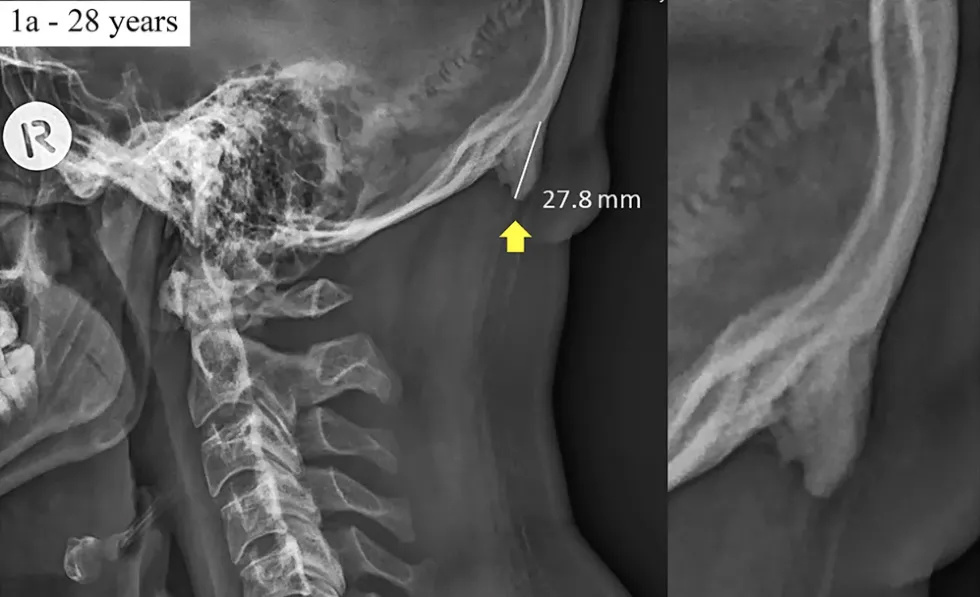

In a paper published earlier this year in Scientific Reports, they observed hornlike spikes growing in the back of people’s skulls that are 10-31mm in length. Shahar notes that bone spurs are considered large if they measure 3-5mm in length. The problem, he continues, is not necessarily the spurs, but the havoc they wreak in the person’s skeletal system.

Three years ago, Shahar and Sayers noticed a troublesome sight in neck X-rays. Enthesophytes, bone spurs protruding from the base of the skull—you can feel them if you check—were appearing in younger patients. Previously seniors that had suffered a lifetime of strain comprised the population for this problem. The team’s first paper, published in 2016, noted that 41 percent of young adults studied (out of 218 X-rays) had noticeable bone growth.

In their latest paper, Shahar and Sayers note that 33 percent of the population (out of 1,200 X-rays) now exhibits enthesophytes. This postural deformity results in chronic headaches and upper back and neck pain.